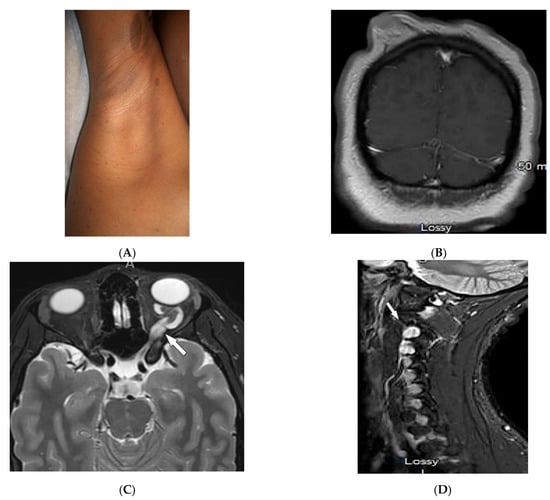

| Behcet’s disease | Oral and genital ulcers Ocular findings Vasculitis CNS lesions | Thickening of the aorta and SVC Bilateral pulmonary artery aneurysms Basal ganglia and brainstem lesions |